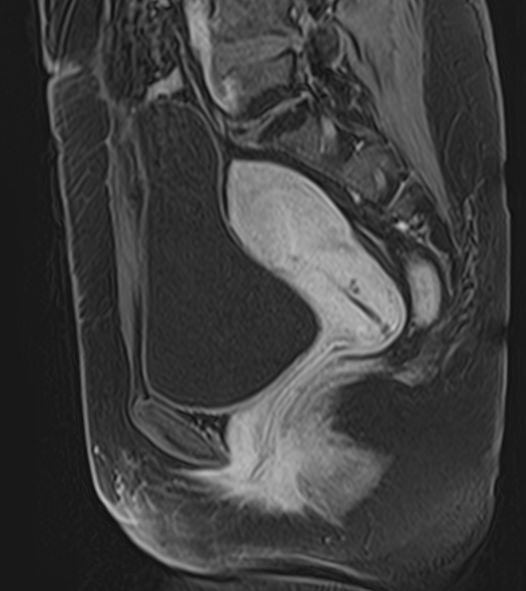

Магнитно-резонансная томография органов малого таза включает в себя исследование женских половых органов (матка, яичники), мужских половых органов (предстательная железа, семенные пузырьки, семявыносящие протоки), мочевого пузыря с мочеточниками, прямой кишки, тазовой брюшины, лимфатических узлов, мягких тканей малого таза.

В нашей клинике исследование выполняется на современном высокопольном томографе экспертного класса TOSHIBA VANTAGE TITAN 1,5 Тесла. Высокая индукция магнитного поля обеспечивает повышенную четкость изображений и превосходную детализацию анатомических структур. Аппарат производит сканирование в трех взаимоперпендикулярных плоскостях и послойными срезами с шагом от 1 мм, что позволяет визуализировать структуру органов и тканей малого таза в мельчайших подробностях.

Инновационные компьютерные программы преобразуют данные, полученные при сканировании, в 3D-изображения исследуемых органов. Методика трехмерной реконструкции используется для улучшения наглядности изображения зоны исследования, тем самым, повышает достоверность диагностики.

Выполнение МРТ малого таза в стандартном режиме возможно без использования контраста. Однако при подозрении на патологические изменения со стороны органов мужской или женской половой сферы, мочевыделительной системы, прямой кишки или окружающих мягких тканей, обязательным является введение контрастного препарата, имеющего в своем составе металл гадолиний. Степень и характер накопления контрастного препарата в органах и тканях позволяет различать патологические процессы, в том числе, диагностировать опухоли. Это используется для диагностики онкологических заболеваний на ранних стадиях, что имеет решающее значение для жизни и здоровья пациента.